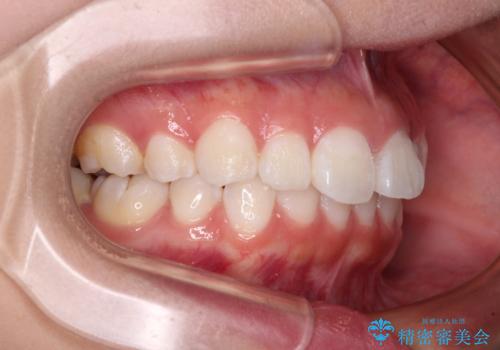

- 上下前歯の叢生を気にして来院された患者様です。

インビザラインでの治療を希望されていて、デコボコの程度が中等度であり、安価なパッケージにて対応可能と判断されたため、インビザライン・モデレートを用いて矯正治療を行うこととしました。